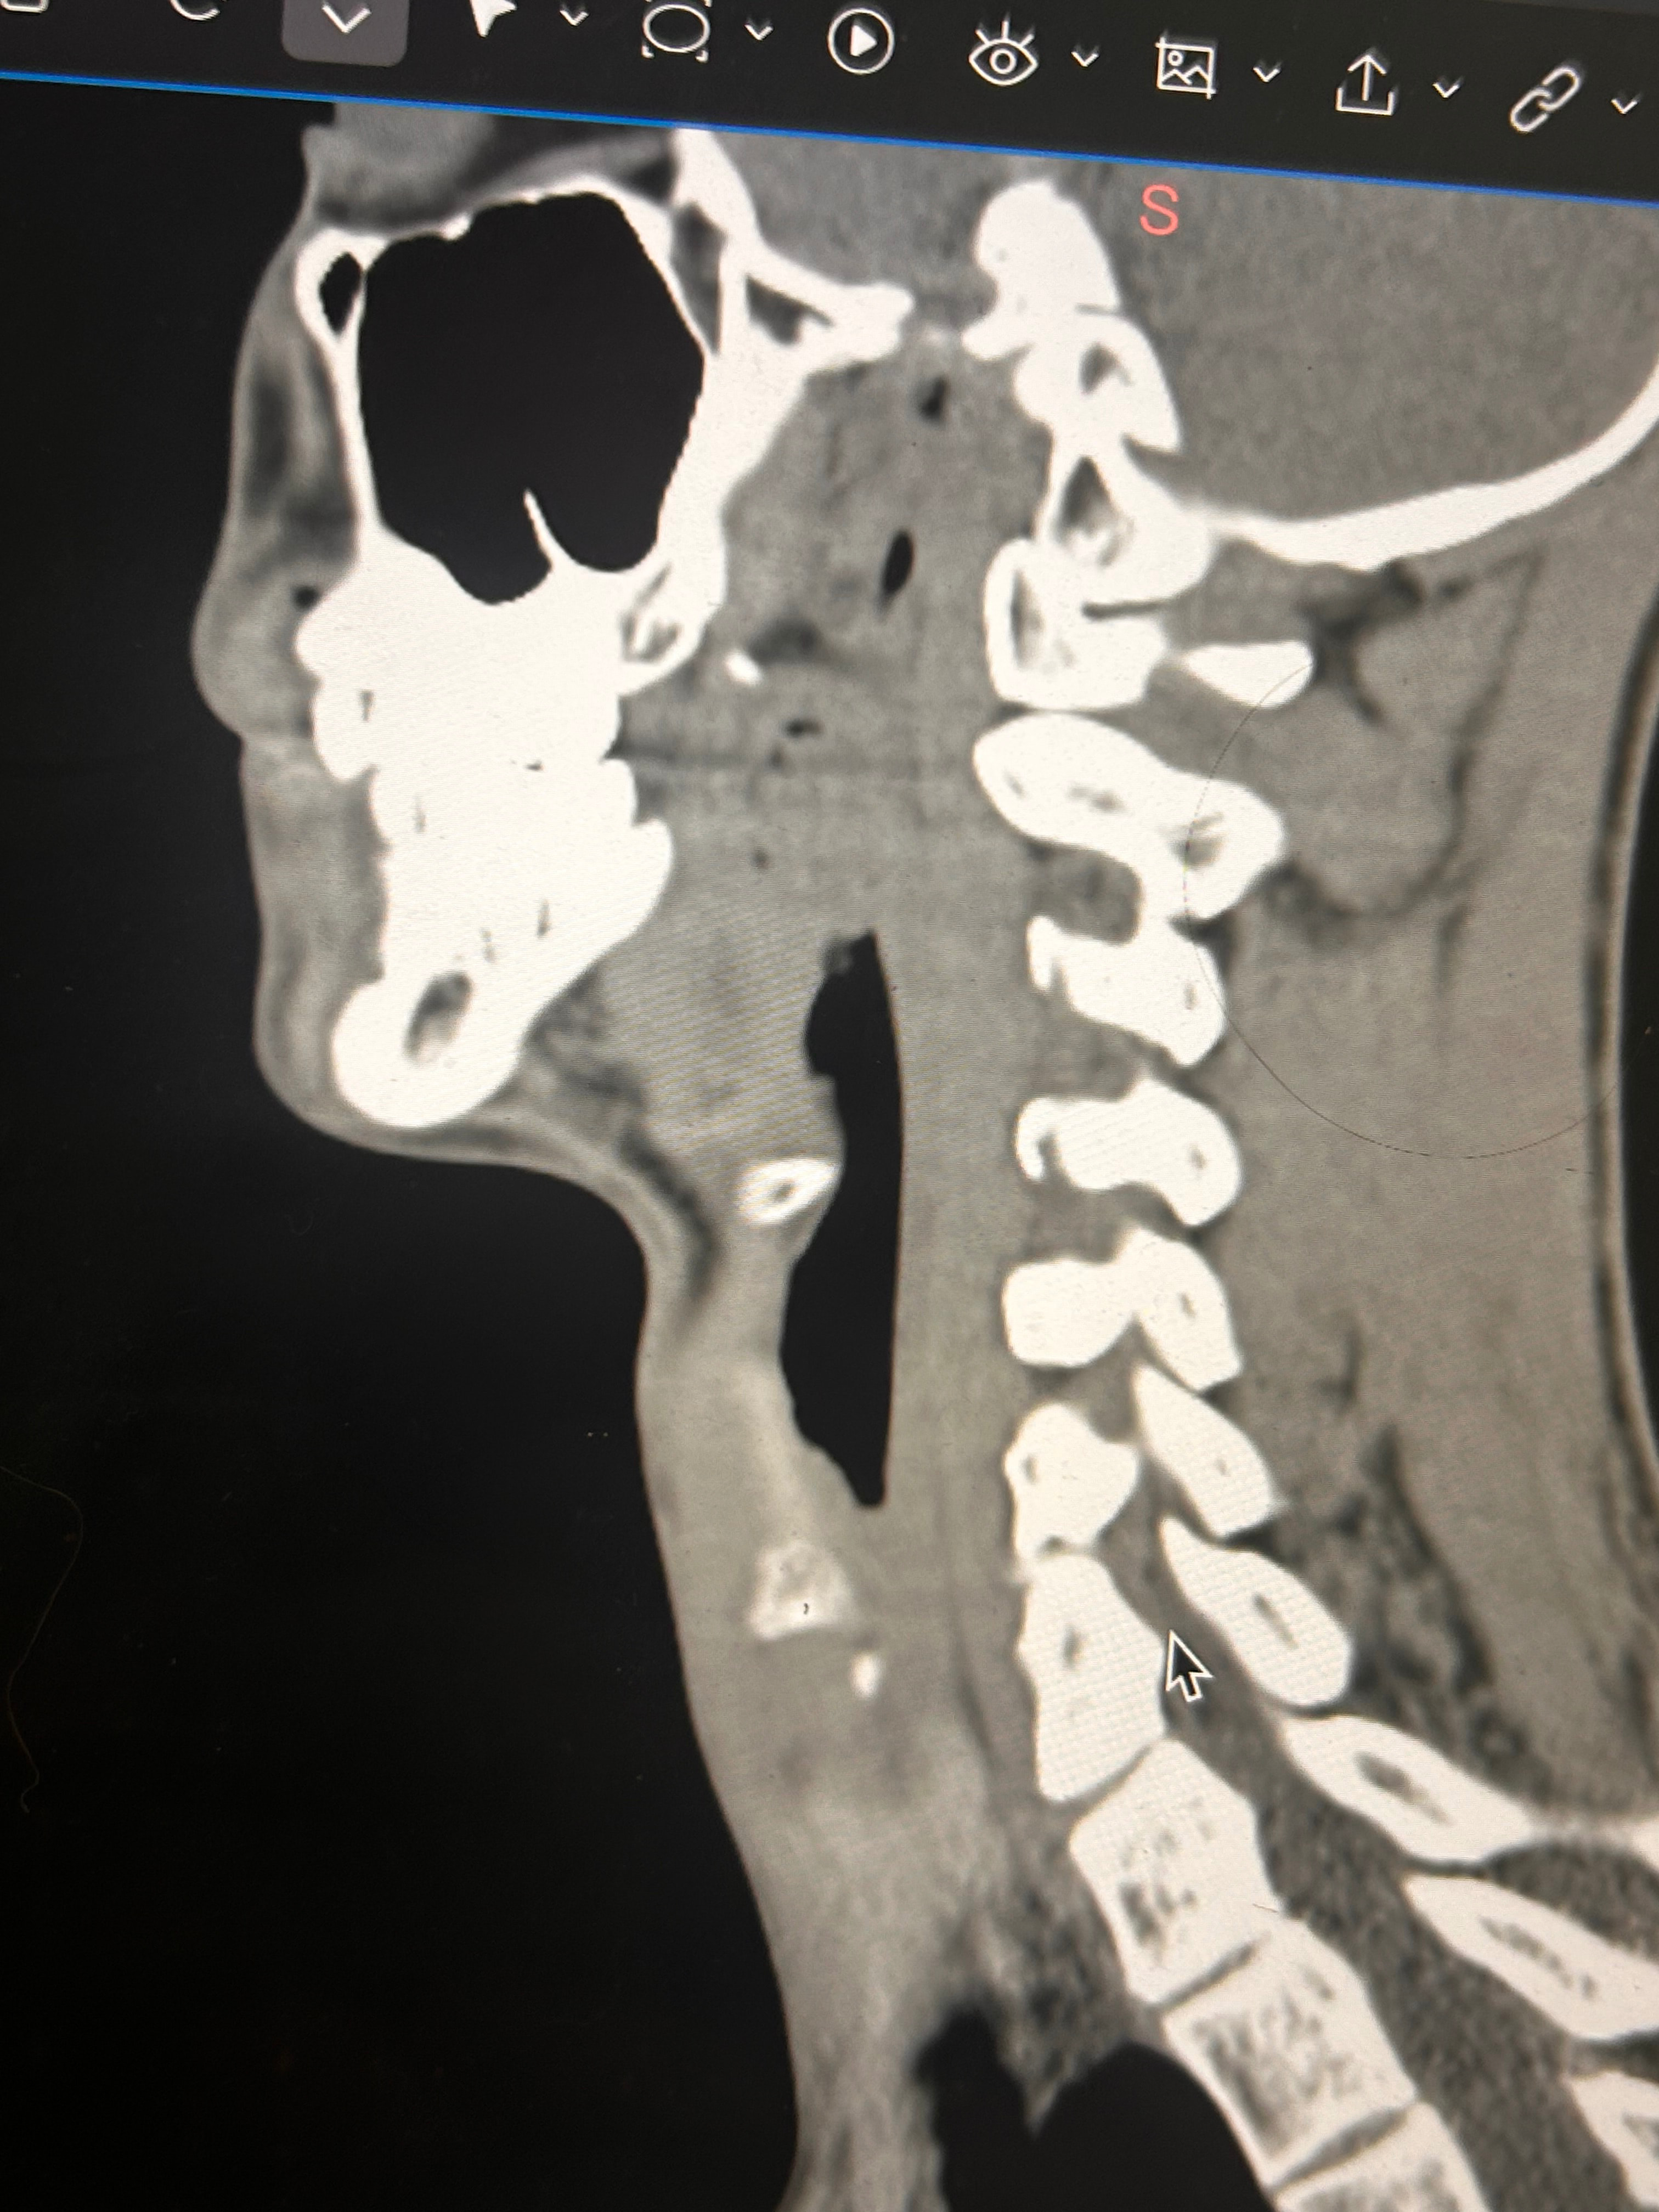

Here are some images of my 3-d ct, thanks for taking an interest it means a lot!

Oh and I almost forgot these were taken before I had my right styloidectomy

Things of note that I can see in your imaging - You’ve completely lost the natural lordotic curve in your cervical spine. That alone can bring the styloids & hyoid bone into closer proximity to nerves & vascular tissues in the neck though it has been speculated that the neck curve is lost when there’s IJV compression due to ES as the body’s way of trying to create more space for the IJV so it can drain the deoxygenated blood from the brain more efficiently. The lordotic curve can be restored w/ gentle exercises but it takes patience & is a slow process. The following link has helpful information about cervical curve restoration.

In this image of your left styloid, it appears from the angle of the picture that your left styloid is extremely close to the left transverse process of C1 (green circled area). If that’s truly the case, your left IJV is likely being squashed between the two & that means your vagus nerve is most likely being squashed at that point, too. Some of your symptoms could be vagal related. Also due to the angle of the image, it appears the greater horn of your hyoid could be very close to your spine which can cause internal/external carotid artery compression but can also cause symptoms that point to hyoid bone syndrome as you’ve suggested. Unfortunately, it doesn’t appear the CT scan was done w/ contrast as none of your veins or arteries appear in the images you posted & contrast is necessary to see those.

I could give you more precise information if your styloids, hyoid & C1 were shown in the sagittal plane (from the side) vs. from behind as they are. Below is a picture showing the anatomical planes of the human body:

I’ll just add in as well that in your first image, the hyoid bone processes look pretty thick, more than you’d expect, so could well be part of your issues, but I do agree with @Isaiah_40_31 that your left styloid is very close to the C1 process, the right side looks a little longer than average… Also looking at the 1st & last images (I’m sorry, | can’t label them for you), there’s calcification below your hyoid which I’m presuming is the thyroid cartilage, it lookd pretty chunky compared to most people’s, so this could possibly be causing some issues too?

Here are some of my 2-d scans, thanks. The top one is my right greater horn and the bottom is the left

I totally missed that I could see your whole hyoid bone from the front in this image. Jules is right, your greater horns are very thick from top to bottom. You can also see that your left greater horn is pretty straight, but the right one has an upward curve to it. I’m not sure what the calcification is below your hyoid but it’s most likely thyroid since the thyroid sits just below the hyoid in the neck.

In the final two images you sent, the right greater horn is very close to your cervical spine so there’s a good chance it’s causing you some problems as well as possible carotid artery irritation or compression in different head positions. The image of the left one doesn’t show as much of the greater horn so I can’t tell how close to the spine it is. Can you back the left image out a bit so it looks more like the right one?